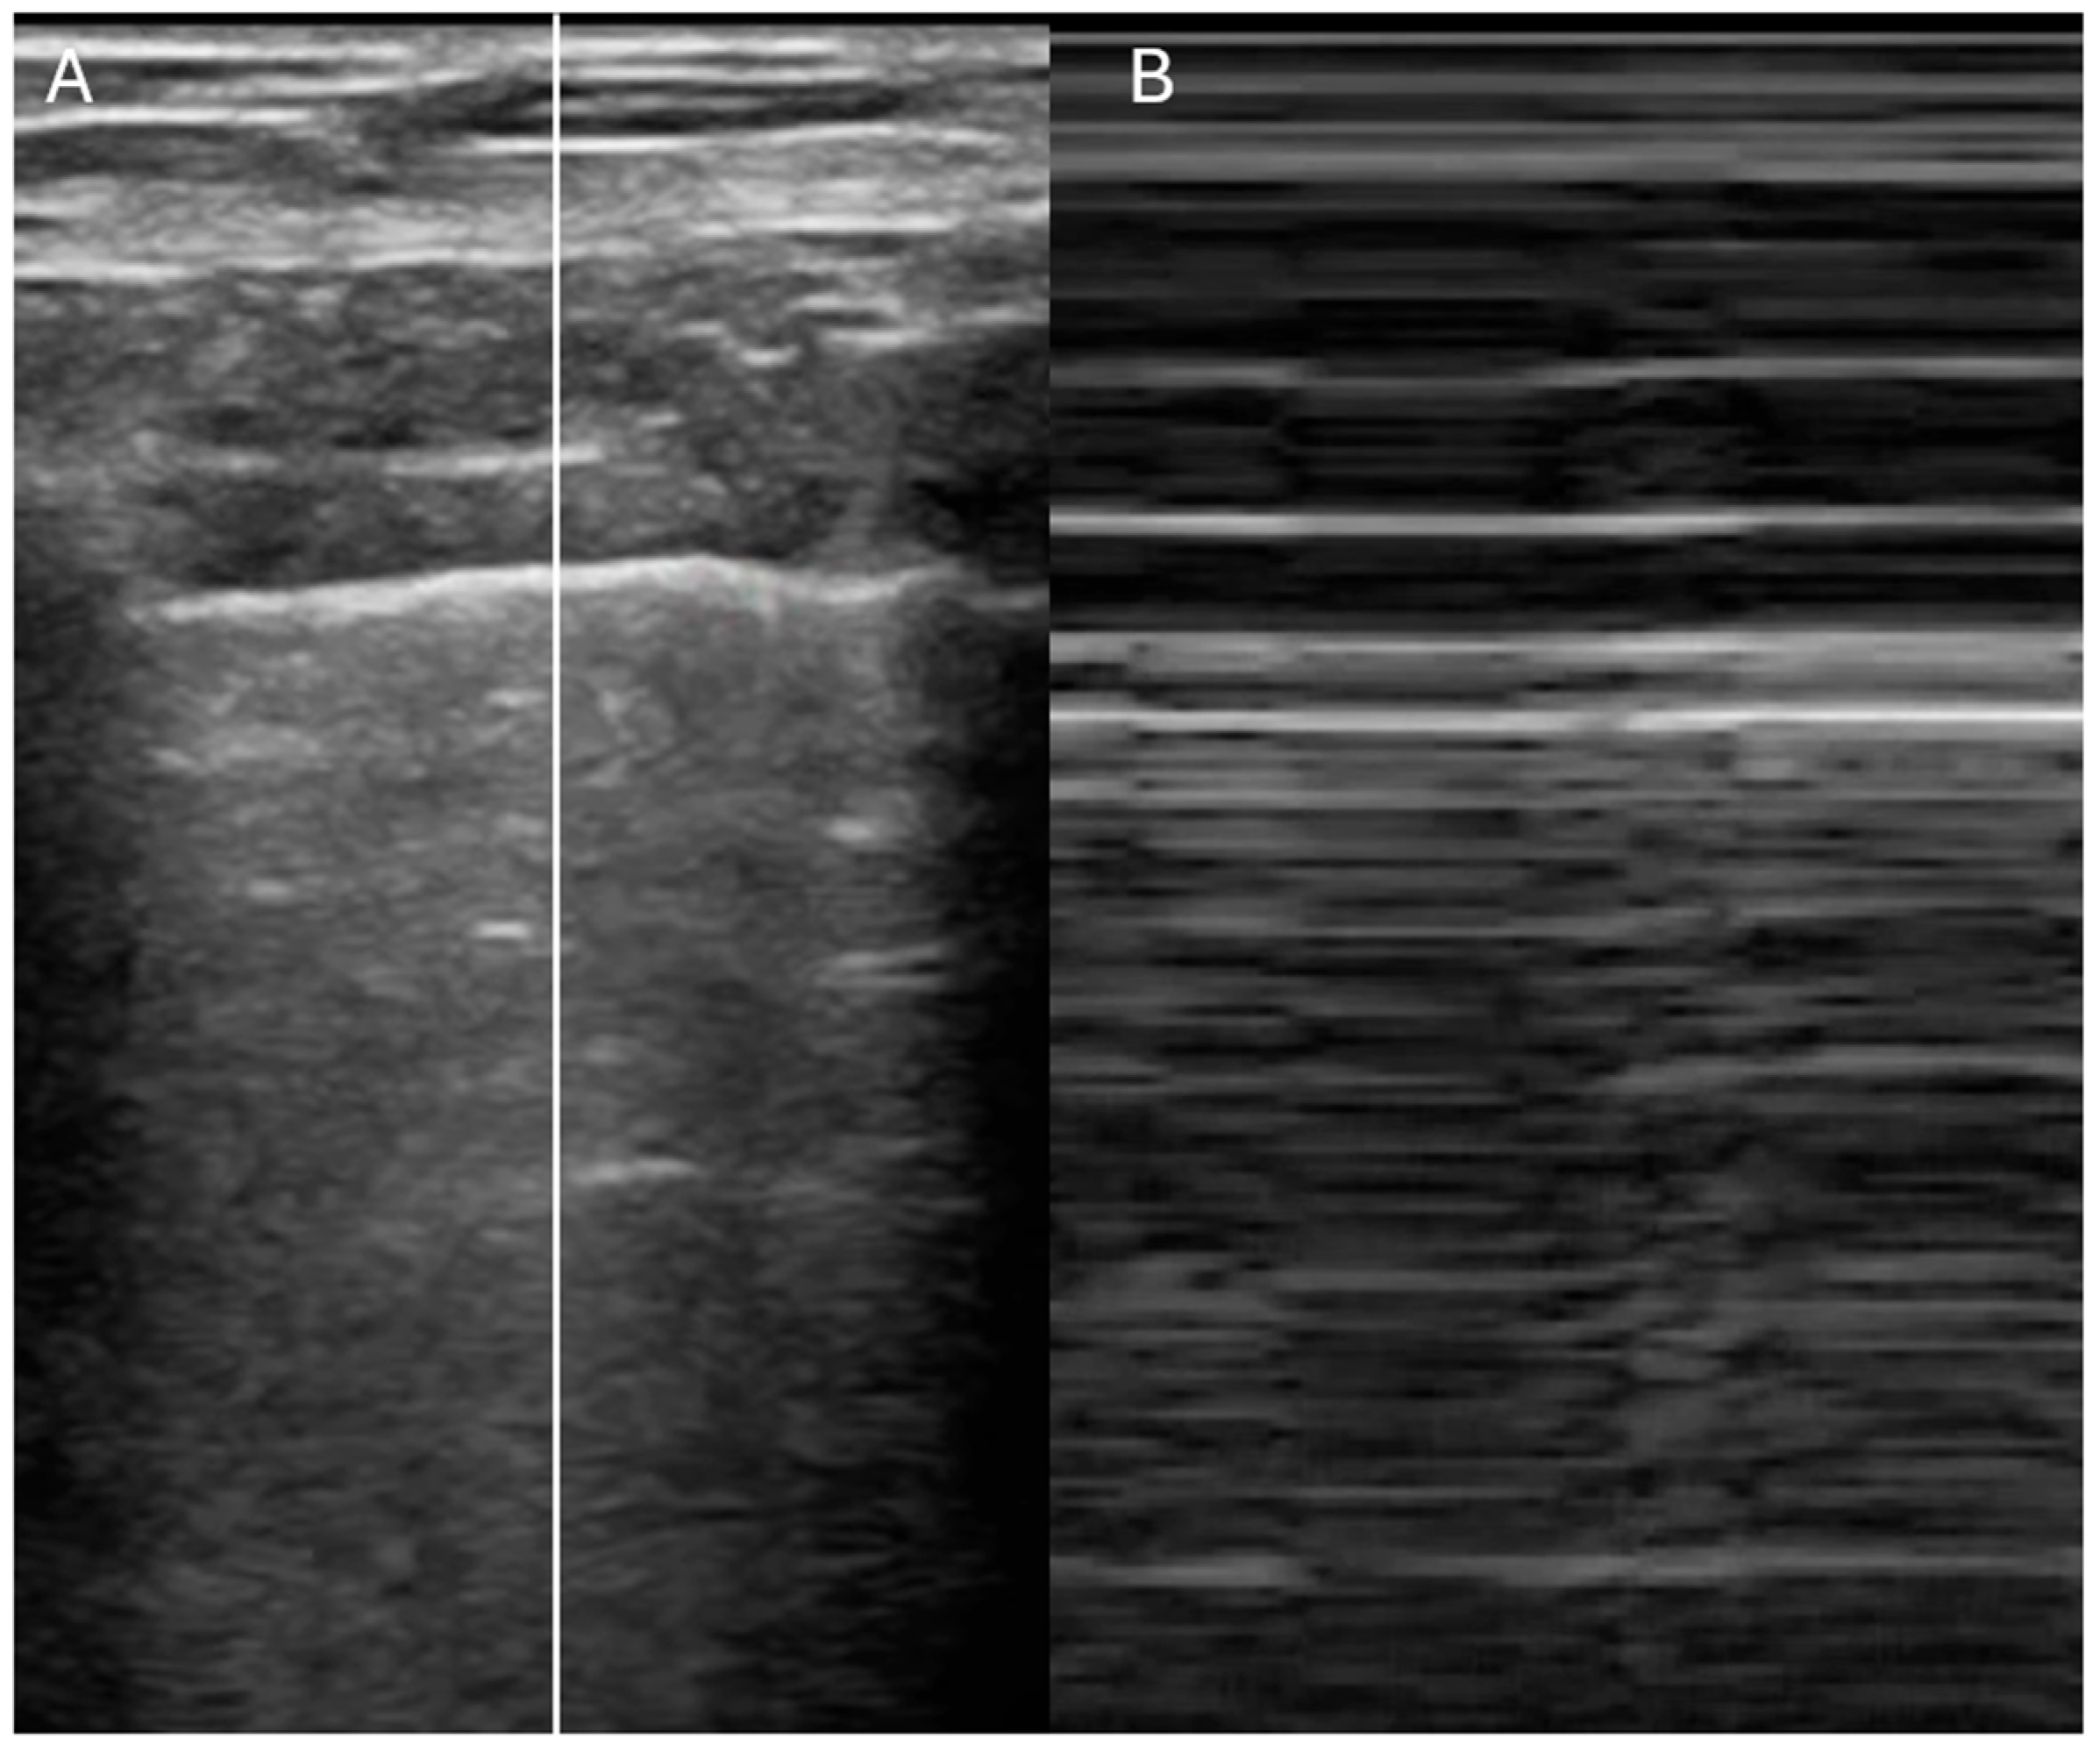

- Is the IVC dilated or collapsible?

- Assessment of right atrial pressure

- Ruge, M.; Marhefka, G.D. IVC measurement for the noninvasive evaluation of central venous pressure. J. Echocardiogr. 2022, 20, 133–143. [Google Scholar] [CrossRef]

- Rudski, L.G.; Lai, W.W.; Afilalo, J.; Hua, L.; Handschumacher, M.D.; Chandrasekaran, K.; Solomon, S.D.; Louie, E.K.; Schiller, N.B. Guidelines for the echocardiographic assessment of the right heart in adults: A report from the American Society of Echocardiography endorsed by the European Association of Echocardiography, a registered branch of the European Society of Cardiology, and the Canadian Society of Echocardiography. J. Am. Soc. Echocardiogr. 2010, 23, 685–713. [Google Scholar]